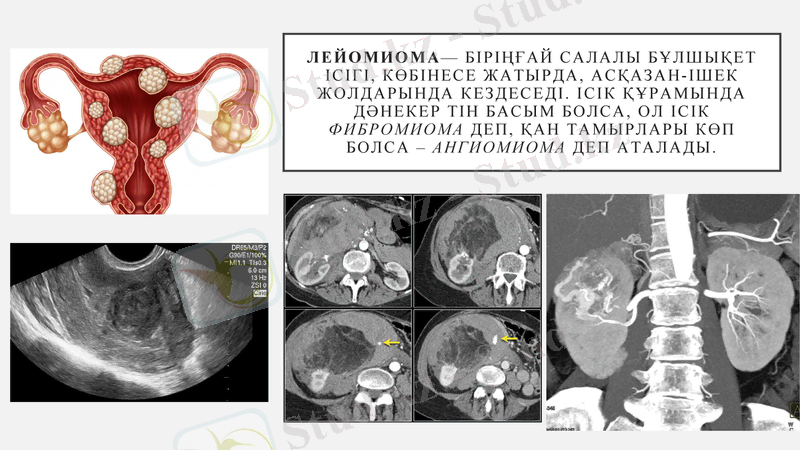

Лейомиома- біріңғай салалы бұлшықет ісігі, көбінесе жатырда, асқазан-ішек жолдарында кездеседі. Ісік құрамында дәнекер тін басым болса, ол ісік фибромиома деп, қан тамырлары көп болса - ангиомиома деп аталады.